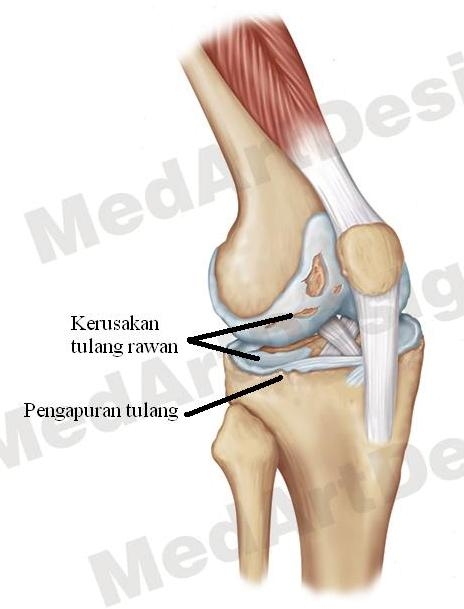

Kenali Gejala Nyeri Lutut Akibat Pengapuran dan Cara Menyembuhkannya

Kenali Gejala Nyeri Lutut Akibat Pengapuran dan Cara Menyembuhkannya